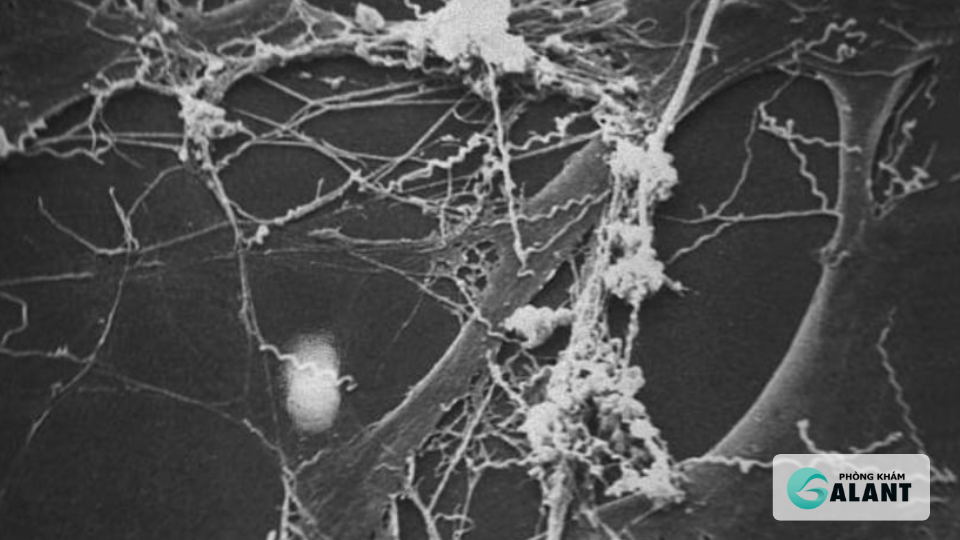

Vi khuẩn Treponema pallidum gây:

- Viêm mạn tính lớp áo giữa của động mạch (mesaortitis)

- Thoái hóa sợi đàn hồi của thành mạch